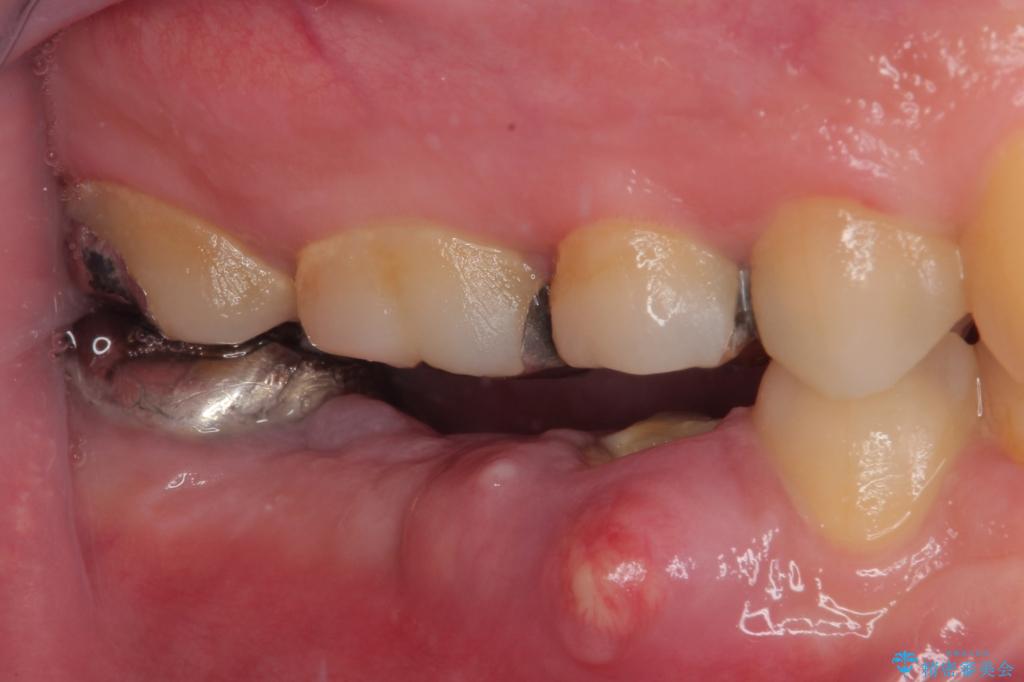

抜歯即時埋入部と後方の欠損部は、即日荷重(インプラント埋入と同時に仮歯を装着すること)が可能な安定値が得られましたが、長い期間欠損した状態で過ごすと、欠損部に舌を押し当てる癖が発現してしまい、舌からの側方圧でインプラントが脱離するリスクが著しく高まってしまうため、即日荷重は行いませんでした。

おかげでインプラントは無事に生着し、僅か4ヶ月で治療を終えることができました。